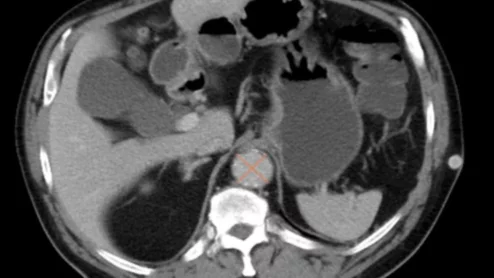

liver cancer

The added indications make the treatment the first Y-90 therapy approved for both unresectable hepatocellular carcinoma and metastatic colorectal cancer of the liver.